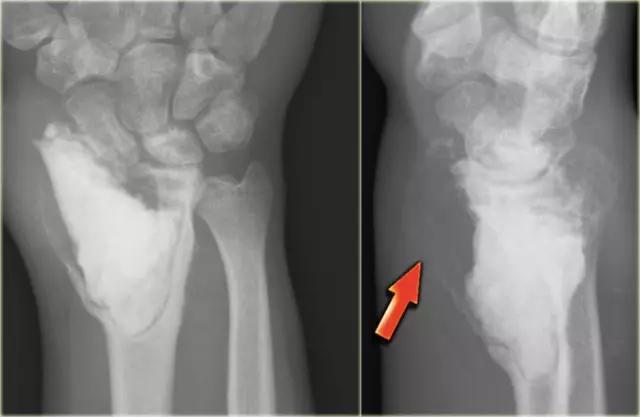

在股骨的骨干的尤因氏肉瘤。注意边界欠清(蓝色箭头)和骨膜反应(红色箭头)。

上图是年轻患者股骨中不明确的溶解性病变。存在具有不规则皮层破坏的渗透性破坏形态。有一个侵略性骨膜反应(箭头)。